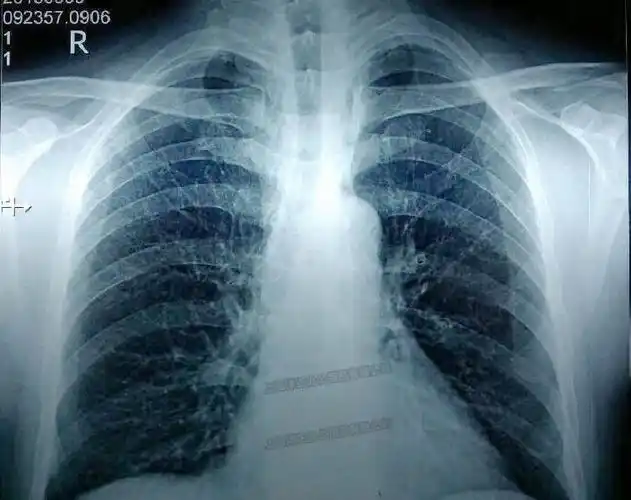

阿娇导医 |x光片能筛查出早期肺癌吗?